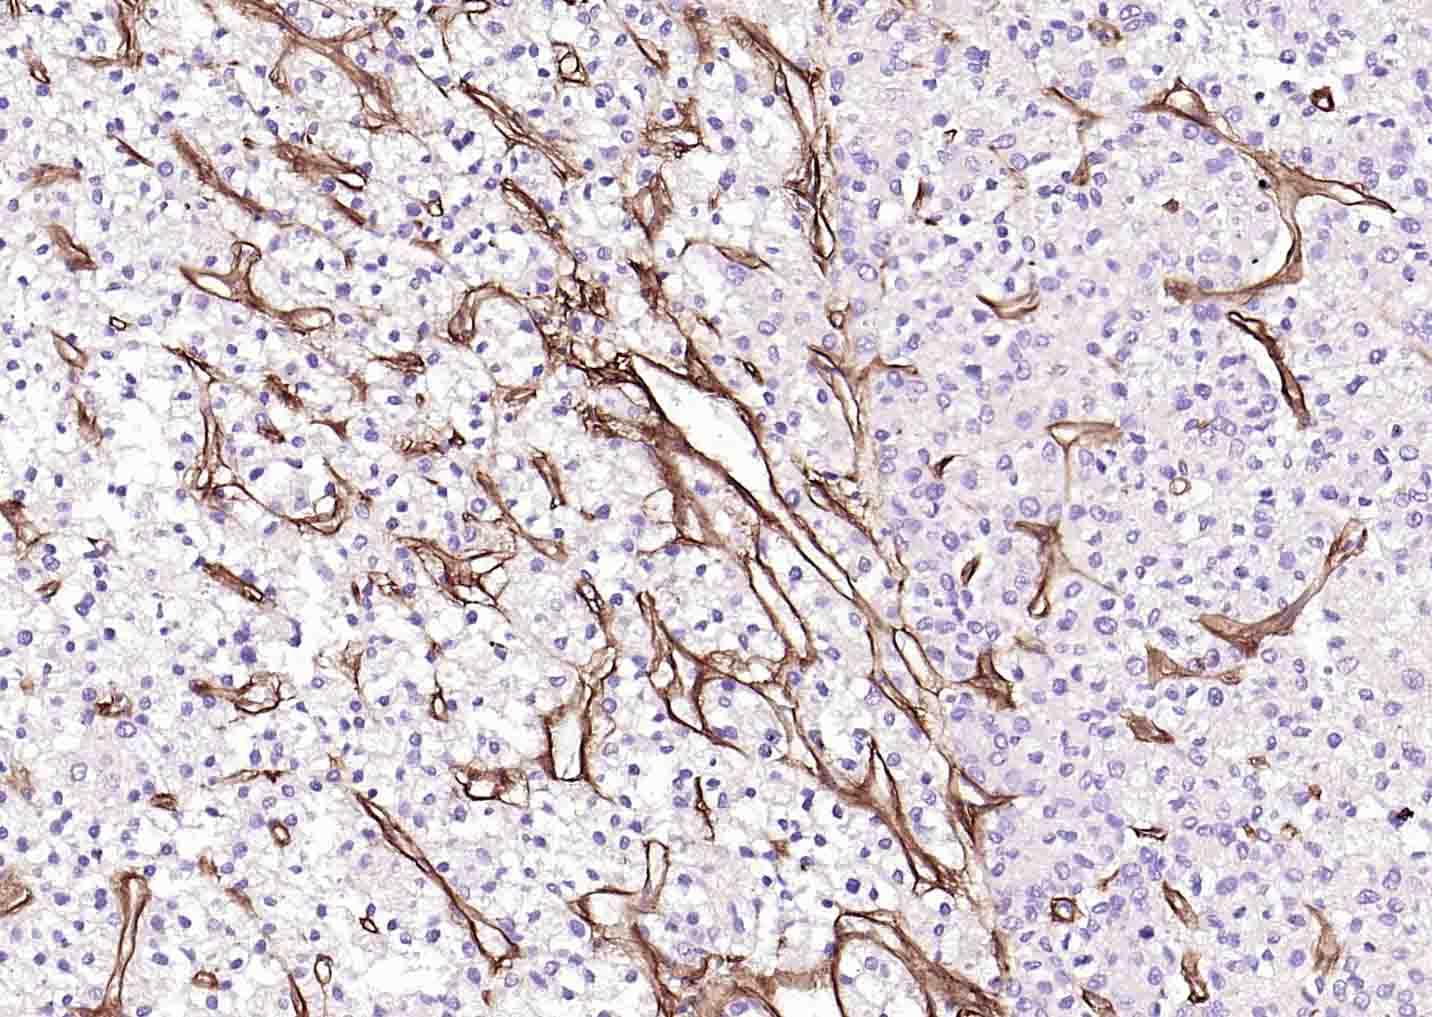

Paraformaldehyde-fixed, paraffin embedded (human liver carcinoma); Antigen retrieval by boiling in sodium EDTA buffer (Ph9.0) for 15min; Block endogenous peroxidase by 3% hydrogen peroxide for 20 minutes; Blocking buffer (normal goat serum) at 37°C for 30min; Incubation with (Collagen IV) Monoclonal Antibody, Unconjugated (bsm-56208R) at 1:500 overnight at 4°C, followed by operating according to SP Kit(Rabbit) (sp-0023) instructionsand DAB staining.

Paraformaldehyde-fixed, paraffin embedded (human lung carcinoma); Antigen retrieval by boiling in sodium EDTA buffer (Ph9.0) for 15min; Block endogenous peroxidase by 3% hydrogen peroxide for 20 minutes; Blocking buffer (normal goat serum) at 37°C for 30min; Incubation with (Collagen IV) Monoclonal Antibody, Unconjugated (bsm-56208R) at 1:500 overnight at 4°C, followed by operating according to SP Kit(Rabbit) (sp-0023) instructionsand DAB staining.